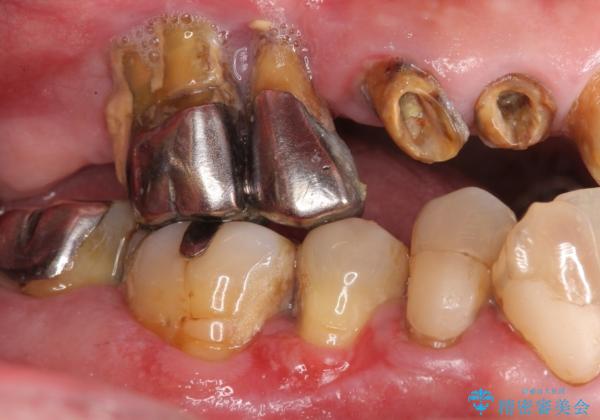

- 歯がぐらぐらで咬めないことを主訴に来院された患者様です。

他院では上顎骨が薄いためインプラントできないと言われたとのことでした。

精査したところ、歯周病に罹患した歯を長年放置したことから骨吸収が進行し、上顎骨の厚みはとても薄くなっていました。

全顎的な歯周病治療を行ったのち、上顎洞底挙上術(上顎骨に骨を増やす手術)を併用したインプラント埋入を行いました。